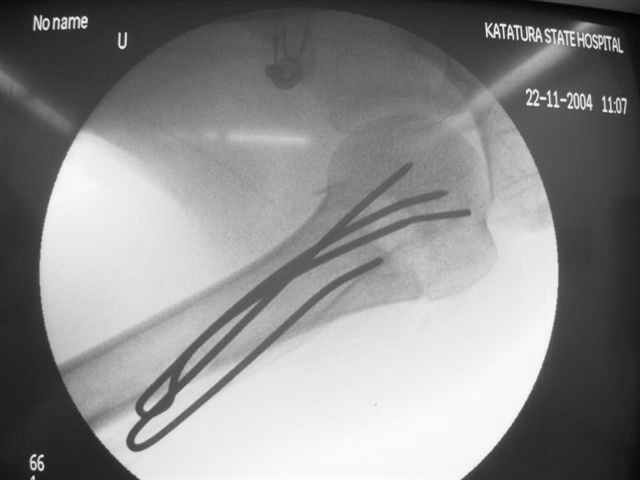

Здравствуйте, Евгений. В используемых Вами методиках остеосинтеза переломов хирургической шейки плечевой кости имеются ряд недостатков. Метод Лазарева хорош, как малоинвазивное вмешательство, но автор умалчивает о таких осложнениях как миграция спиц. Консолидация перелома начинается с резорбции костной ткани в месте перелома, в связи с этим спицы выходя за пределы субхондрального слоя головки плеча, и мигрируют в полость сустава, обеспечивая импиджмент синдром. Накостные фиксаторы (какие бы они не были) чаще используются для открытого остеосинтеза, что неизбежно ведёт к нарушению кровообращея в головке, далее к элементам асептического некроза с вытекающими последствиями. Обратите внимание на метод спирального остеосинтеза, который по философии отвечает принципам остеосинтеза при низкой минеральной плостности кости. Эту методику я внедрил 2 года назад, и она себя оправдывает. Статью по этому поводу Вы можете найте в сборнике съезда травматологов России, которых был в Саратове. (см фото) С Уважением, Комков Андрей.

Просмотрел приложенный снимок пенетрации спиц в сустав. Мне кажется, здесь были некоторые отклонения от рекомендованного доктором Лазаревым варианта. Метод называется "фиксация напряженными спицами", т.е после внедрения в головку концы спиц расходятся! А следующий фиксатор укрепляет позицию, удерживает от смещения! Поэтому, чем больше спиц, тем лучше создается жесткость и это предупреждает миграцию.

В Вашем случае получилась обычная фиксация спицами, т.е. спицы вошли в головку параллельно и не раздвинулись! В прошлом примеры идеальной установки напряженных спиц, кроме доктора Лазарева, показал Женя Чекашкин из Намибии.

Возможности фиксатора Лазарева я не идеализирую, и, возможно, другие коллеги также наблюдали случаи миграции, но от этого "феномена" никуда не уйти. Играет роль активность больного и качество кости. Приходилось видеть миграцию не только при малоинвазивных, а также в более устойчивых видах фиксации (пластин с угловой стабильностью).